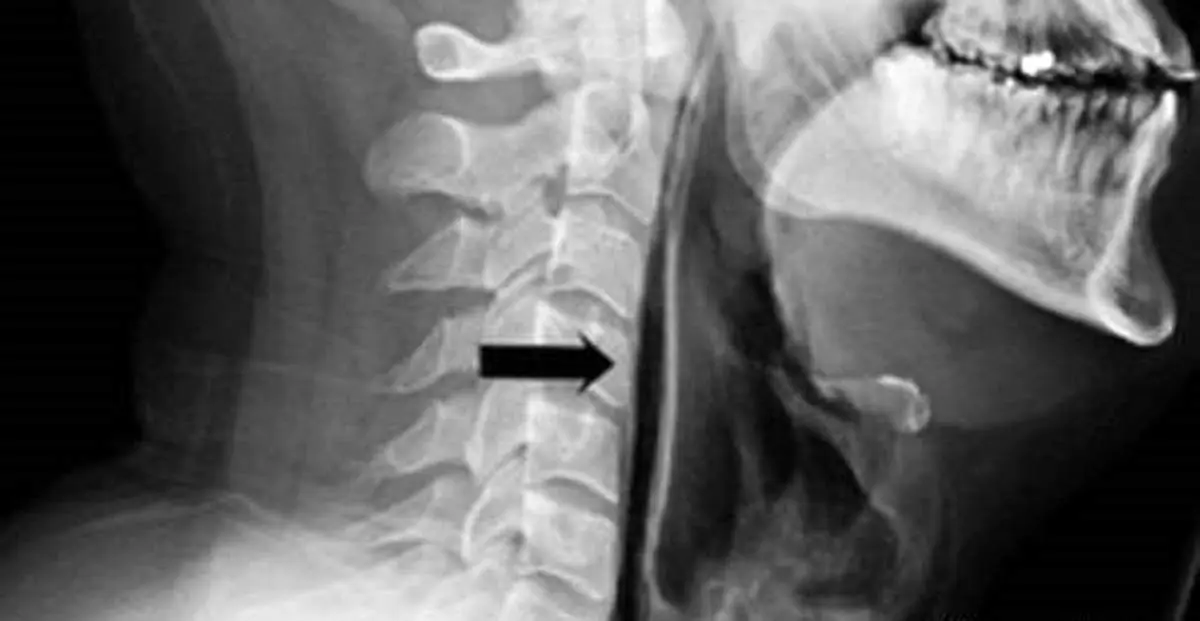

این مرد می گوید بعد از عطسه کردن به این شکل نادرست احساس کرده چیزی در گلویش "ترکیده" و بلافاصله دچار درد شدید و دشواری در تکلم و حتی قورت دادن آب دهانش شده برای همین برای معاینه و درمان به بیمارستان مراجعه کرده است. زمانیکه پزشکان او را معاینه کردند متوجه تورم شدید و درد در ناحیه گردن و گلوی او شدند ، تصویری برداری با اشعه ایکس نشان داد در اثر پارگی ایجاد شده هوا از نای این فرد وارد بافت گلو می شود و علت درد و مشکل در بلع نیز همین بوده است.